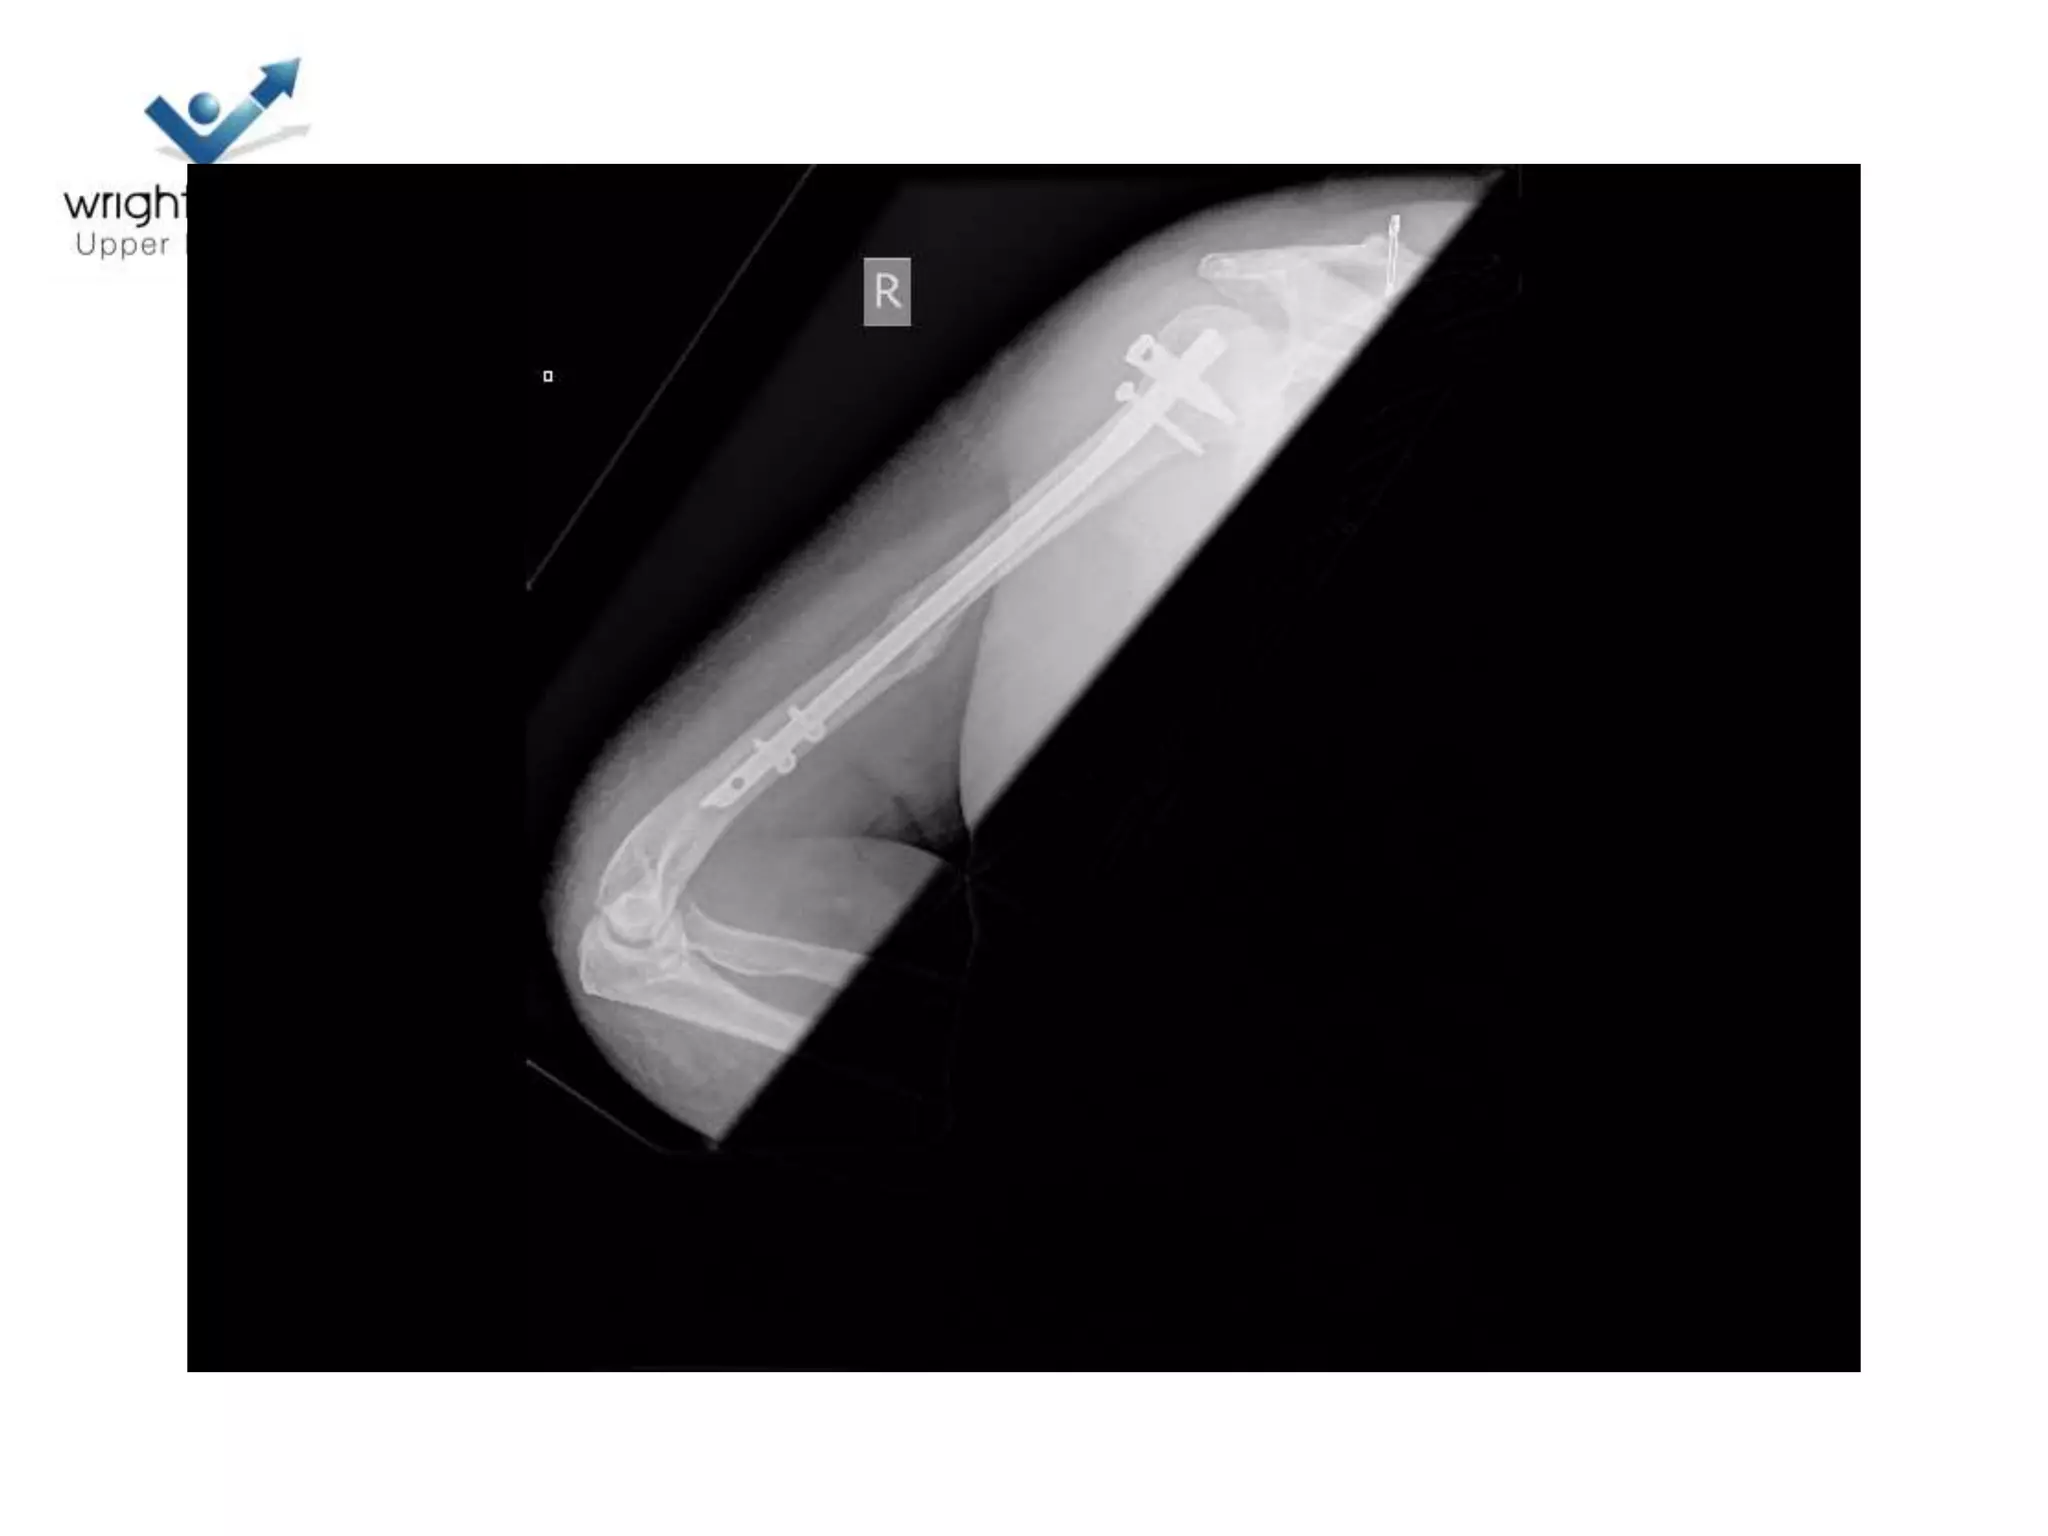

Prox humeral nail: top tip

Image Courtesy: AO

Locking plate; Tips

• Positioning

Locking plates: Tips

• Rotator cuff control

Images courtesy: AO

Locking plate: Tips

• Belts and braces